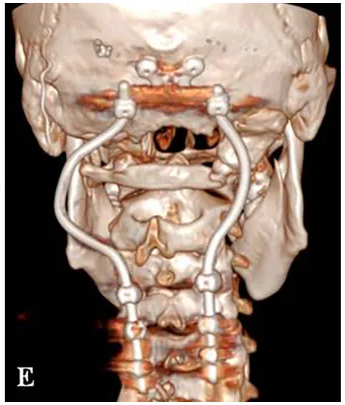

术后三维CT显示C0-C3-C4-C5枕颈融合稳定,根钉的弯曲设计有助于PBRT放疗的实施。